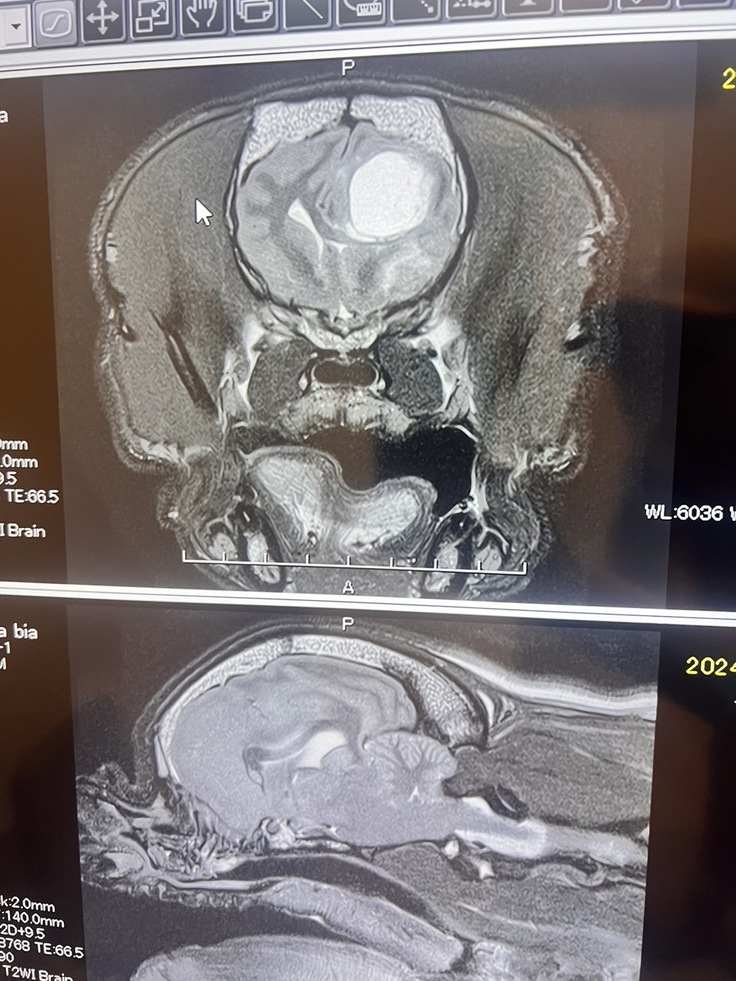

ビアくんは、フレンチブルドッグが罹りやすい、脳腫瘍(グリオーマ)が頭の中に出来てしまいました。

初めてのてんかんから、ちょうど1ヶ月後、3回目のてんかんを起こしました。1回目のてんかんと症状はほぼ同じでしたが、発作時間15分超えで、すぐにMRIの検査を勧められ、MRI検査を受けに行きました。

検査結果は脳腫瘍。

グリオーマ(希突起膠細胞腫)という症例も少ない腫瘍でした。

腫瘍は右脳に出来ていたため、左上下肢の麻痺が出ていました。腫瘍があることで脳が圧迫され通常では隙間があるところに隙間も無く脳圧が高い状態。ビアくんは頭痛が出現していて元気もなくなり、頭が上がらなくなって抑うつ状態になっていました。

また、脳ヘルニアにもなっており、いつ脳圧が上がり脳幹(呼吸、意識など、生命維持に関わる所)を圧迫して危険な状態になるかわからない状況です。